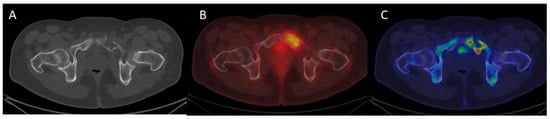

- Role of 18 F-FDG PET/CT in the Diagnosis and Management of Multiple Myeloma and Other Plasma Cell Disorders: A Consensus Statement by the International Myeloma Working Group-Clinical Key. Available online: https://www-clinicalkey-com.proxy2-bib.sdu.dk/#!/content/journal/1-s2.0-S1470204517301894 (accessed on 5 March 2020).

- Zamagni, E.; Nanni, C.; Patriarca, F.; Englaro, E.; Castellucci, P.; Geatti, O.; Tosi, P.; Tacchetti, P.; Cangini, D.; Perrone, G.; et al. A prospective comparison of 18F-fluorodeoxyglucose positron emission tomography-computed tomography, magnetic resonance imaging and whole-body planar radiographs in the assessment of bone disease in newly diagnosed multiple myeloma. Haematologica 2007, 92, 50–55. [Google Scholar] [CrossRef] [PubMed]

- Bartel, T.B.; Haessler, J.; Brown, T.L.Y.; Shaughnessy, J.D.; van Rhee, F.; Anaissie, E.; Alpe, T.; Angtuaco, E.; Walker, R.; Epstein, J.; et al. F18-fluorodeoxyglucose positron emission tomography in the context of other imaging techniques and prognostic factors in multiple myeloma. Blood 2009, 114, 2068–2076. [Google Scholar] [CrossRef]